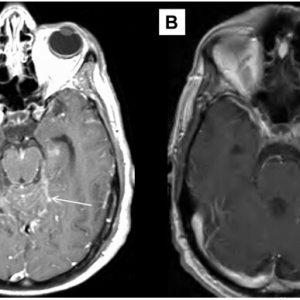

病例学习:神经纤维瘤病2型

近期,AJNR杂志刊登了如下一则教学病例。患者男性,15岁,截瘫。结合上图,考虑如何诊断?A. 播散型星形细胞瘤B. 家族性视网膜及中枢神经系统血管瘤病C. 神经纤维瘤病2型D. 脊柱转移瘤答案:C. 神经纤维瘤病2型图1. ...